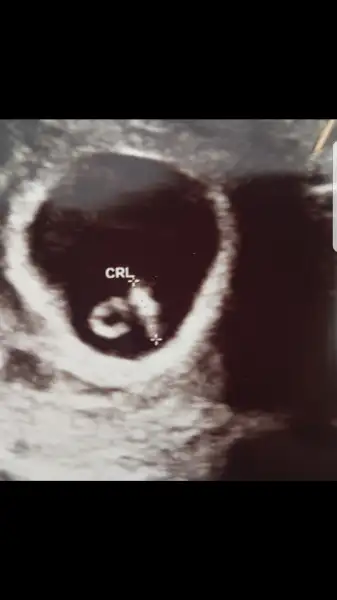

canım kesenin hemen yanında kanama varmış, düşük riski var dedi doktor. ama keseye bir sey olmamış, kalp atışı da var. ritmi güzel dedi. Düşük önleyici hap verdi. tıbbın çaresiz kaldigi durumlar var, biz ne yaparsak yapalım bazen düşükle sonuçlanabiliyor dedi. sagliksiz bir bebek dünyaya getirmek istemez kimse, oyuzden dusukle sonuclanirsa uzulmuyoruz, yeterki sana bir sey olmasın dedi. bence düsmeyecek dedi, bol istirahat verdi. kabızlık, kahkaha atmak, aglamak, cinsellik, vs hepsi yasak ultrason görüntüleri de koyuyorum. Allah nasip etsin evlatlarimizi saglikla kucagimiza alalımS Serpilzorlu naptin canim.

Cok geçmiş olsun canım Rabbim sağlıkla kucağına almayı nasip etsin inşAllahcanım kesenin hemen yanında kanama varmış, düşük riski var dedi doktor. ama keseye bir sey olmamış, kalp atışı da var. ritmi güzel dedi. Düşük önleyici hap verdi. tıbbın çaresiz kaldigi durumlar var, biz ne yaparsak yapalım bazen düşükle sonuçlanabiliyor dedi. sagliksiz bir bebek dünyaya getirmek istemez kimse, oyuzden dusukle sonuclanirsa uzulmuyoruz, yeterki sana bir sey olmasın dedi. bence düsmeyecek dedi, bol istirahat verdi. kabızlık, kahkaha atmak, aglamak, cinsellik, vs hepsi yasak ultrason görüntüleri de koyuyorum. Allah nasip etsin evlatlarimizi saglikla kucagimiza alalım

İnş her şey yoluna girer canım sıkma sen canını hayırlısıyla sağ salim kucağımıza alırız inşcanım kesenin hemen yanında kanama varmış, düşük riski var dedi doktor. ama keseye bir sey olmamış, kalp atışı da var. ritmi güzel dedi. Düşük önleyici hap verdi. tıbbın çaresiz kaldigi durumlar var, biz ne yaparsak yapalım bazen düşükle sonuçlanabiliyor dedi. sagliksiz bir bebek dünyaya getirmek istemez kimse, oyuzden dusukle sonuclanirsa uzulmuyoruz, yeterki sana bir sey olmasın dedi. bence düsmeyecek dedi, bol istirahat verdi. kabızlık, kahkaha atmak, aglamak, cinsellik, vs hepsi yasak ultrason görüntüleri de koyuyorum. Allah nasip etsin evlatlarimizi saglikla kucagimiza alalım

Rabbim sag salim kucagina almayi nasip etsin..canım kesenin hemen yanında kanama varmış, düşük riski var dedi doktor. ama keseye bir sey olmamış, kalp atışı da var. ritmi güzel dedi. Düşük önleyici hap verdi. tıbbın çaresiz kaldigi durumlar var, biz ne yaparsak yapalım bazen düşükle sonuçlanabiliyor dedi. sagliksiz bir bebek dünyaya getirmek istemez kimse, oyuzden dusukle sonuclanirsa uzulmuyoruz, yeterki sana bir sey olmasın dedi. bence düsmeyecek dedi, bol istirahat verdi. kabızlık, kahkaha atmak, aglamak, cinsellik, vs hepsi yasak ultrason görüntüleri de koyuyorum. Allah nasip etsin evlatlarimizi saglikla kucagimiza alalım

masallah canim. sakin ol sakın uzulme. yat dinlen bol bol progestanini ic.canım kesenin hemen yanında kanama varmış, düşük riski var dedi doktor. ama keseye bir sey olmamış, kalp atışı da var. ritmi güzel dedi. Düşük önleyici hap verdi. tıbbın çaresiz kaldigi durumlar var, biz ne yaparsak yapalım bazen düşükle sonuçlanabiliyor dedi. sagliksiz bir bebek dünyaya getirmek istemez kimse, oyuzden dusukle sonuclanirsa uzulmuyoruz, yeterki sana bir sey olmasın dedi. bence düsmeyecek dedi, bol istirahat verdi. kabızlık, kahkaha atmak, aglamak, cinsellik, vs hepsi yasak ultrason görüntüleri de koyuyorum. Allah nasip etsin evlatlarimizi saglikla kucagimiza alalım